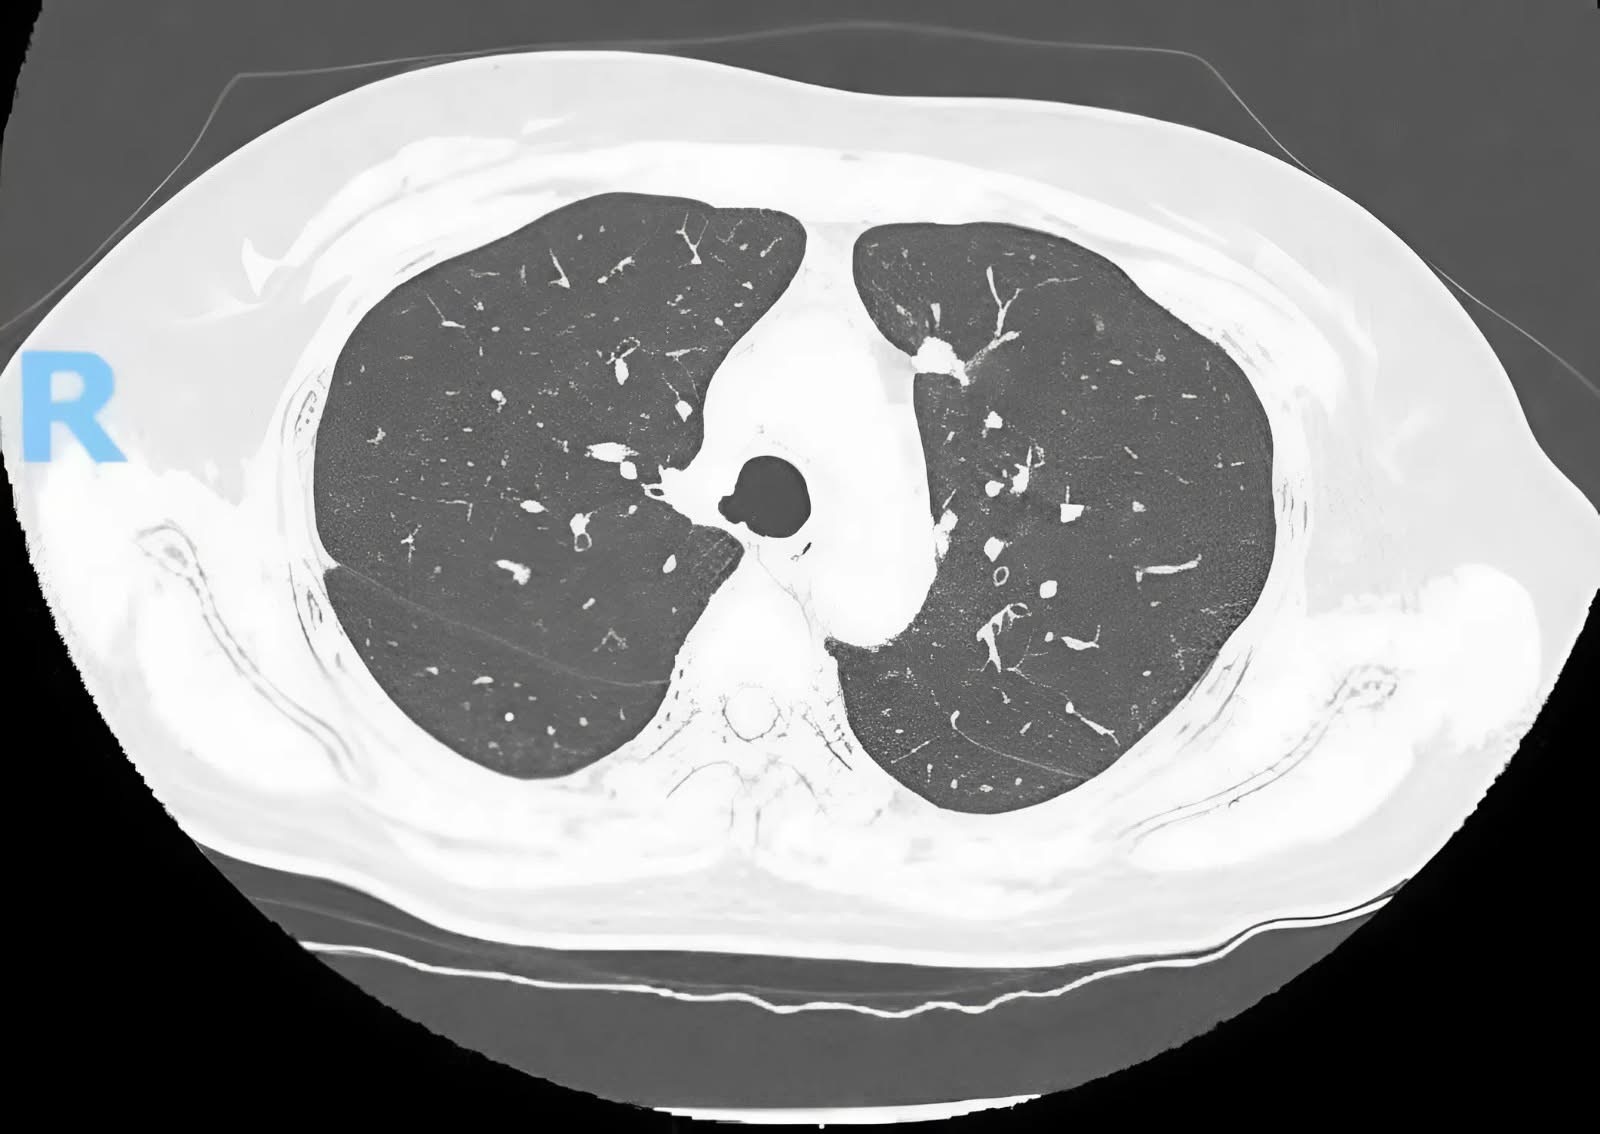

Trường hợp thứ 2 là bệnh nhân L.T.H. (55 tuổi, ngụ TP.HCM) được phát hiện nốt mờ 9 mm ở phân thùy sau thùy trên phổi phải qua chụp CT ngực độ phân giải cao (HRCT). Sau đó, bệnh nhân được ekip bệnh viện Chợ Rẫy hội chẩn với chẩn đoán là ung thư phổi giai đoạn sớm (T1aN0M0) và có chỉ định phẫu thuật nội soi cắt thùy phổi bằng robot, kèm nạo hạch triệt để.

Một ngày sau phẫu thuật, bệnh nhân H. được rút dẫn lưu màng phổi, các chỉ số sức khỏe ổn định. Sau 4 ngày phẫu thuật thì bệnh nhân đã được xuất viện.

Kết quả giải phẫu bệnh cho thấy carcinoma tuyến biệt hóa tốt, không di căn hạch, diện cắt âm tính. Sau 2 năm theo dõi, bệnh nhân hoàn toàn khỏe mạnh và không có dấu hiệu tái phát.